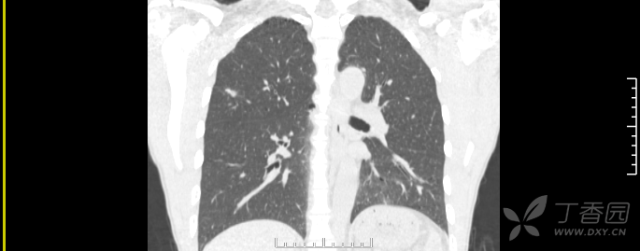

两肺多原发癌